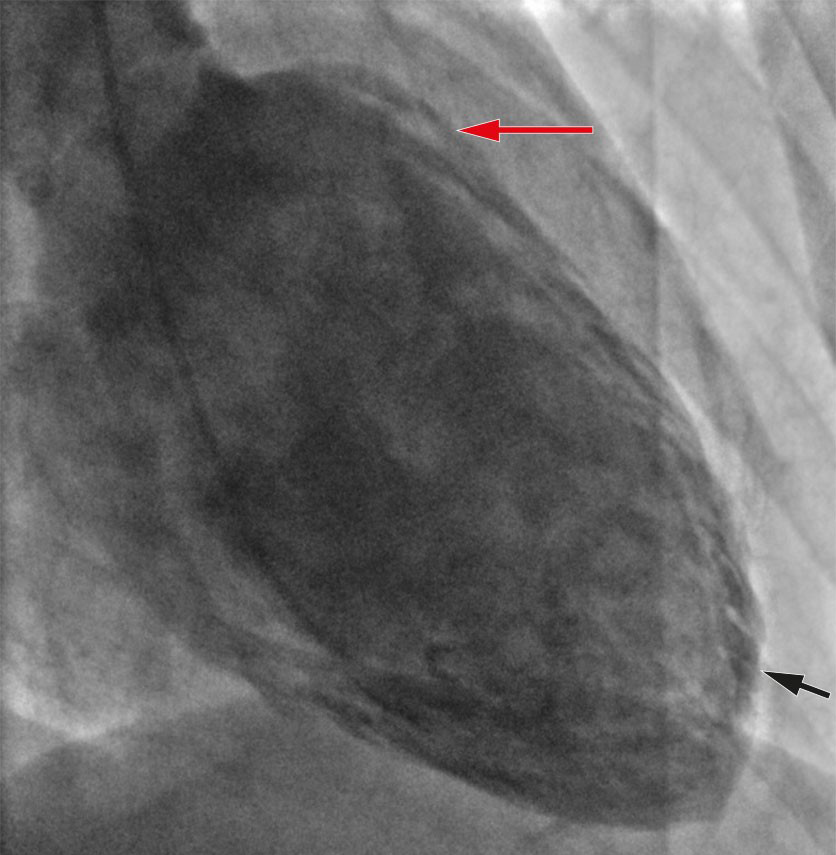

Koronarangiografi viste normale koronararterier, og ventrikulografi viste hypokinesi apikalt og hyperkontraktilitet basalt, typisk for takotsubosyndrom (Figur 2). Samme kveld ble det startet opp behandling med 1,25 mg ramipril.